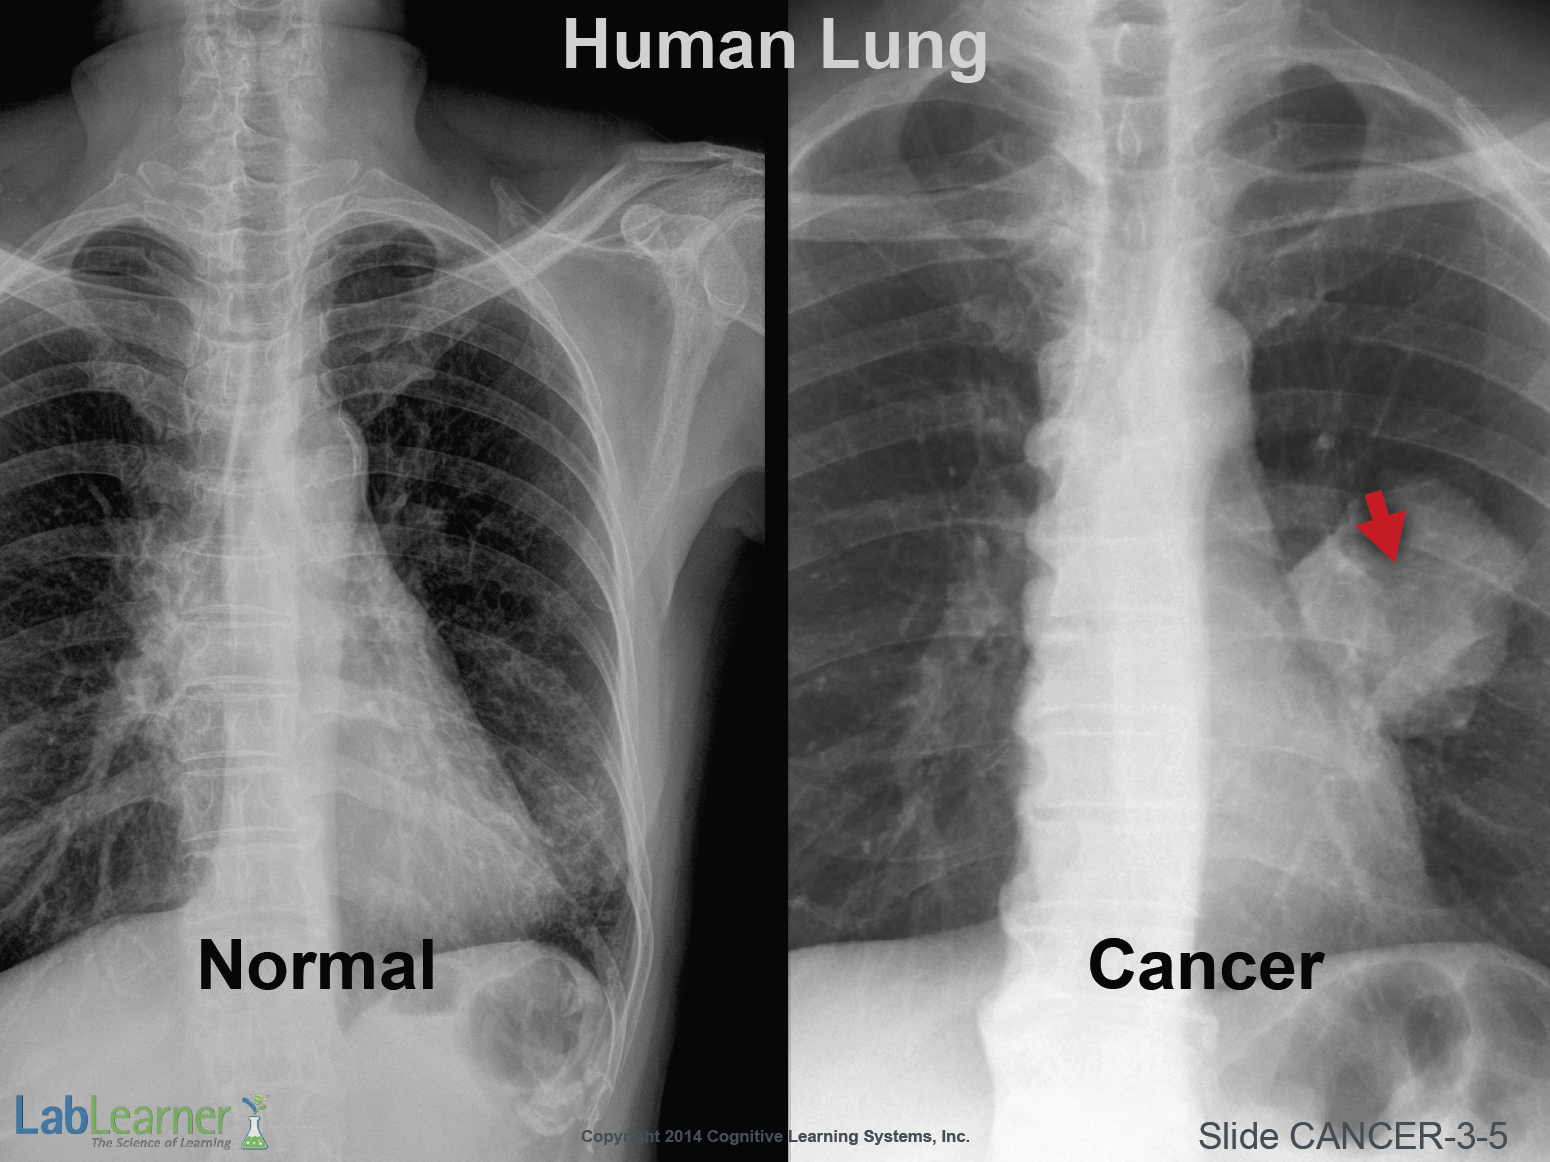

SLIDE CANCER-3-5

- We now turn to a look at two very specific types of cancer; lung and breast cancer. Students will be able to examine both normal and cancerous examples of these human tissues in Investigation 3 lab.

- This slide shows a normal chest x-ray on the left and an x-ray from a patient with lung cancer on the right. The mass or tumor is rather large and highlighted by the red arrow.

Note: For reference, the large mass to the right of the vertebral column in both x-rays is the heart. Below the lungs, the diaphragm and organs of the abdomen are seen.